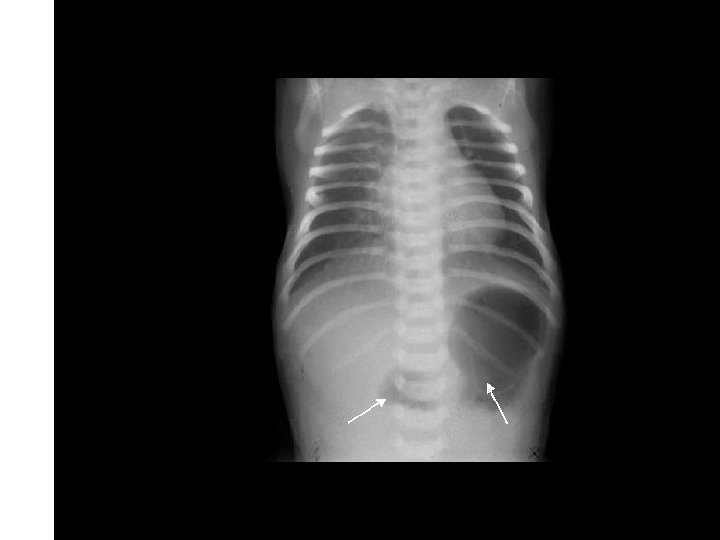

Case 1 Day 12 • On day 12 an Xray was done……

Case 1 Isolated GI Perforation • Not the same as NEC • Increased incidence with: – Low gestational age – Hydrocortisone – Combined Indomethacin & Hydrocortisone – Isolated Indomethacin not a risk factor (? ) • Symptoms secondary to peritonitis • Heals spontaneously – Risk for strictures

Case 1 Oh, oh…. . • On day 12…. – Free air noted on abdominal XR – No clinical abdominal symptoms • Rx…. – Intubated for transport – NPO – Antibiotic coverage expanded – Transported to Oakland Anna Bergquist CHO MR 960776